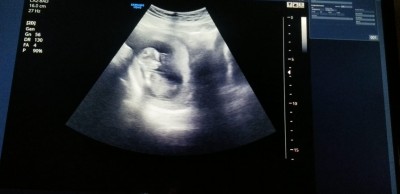

cınsıyet tahmin edebilen varmii

cinsiyet tahmini yapabilir misiniz kızlar

12+2

Erkekmiki o tahminden anlamam icimden geceni yazmak istedim:)

Erkek gibi hayırlısı olsun

erkek gibi hissettim :)

Bende kız diyeyim bari bu aralar herkesin kızı olacakmis gibi herkese kız diyorum Rabbim sağlıklı evlatlar nasip etsin canım bu benim içimden geçen Bu arada fotoda bı çıkıntı var ama bebişin bacağımııı yoksa pipisi mı bilemedim tabi :)

kız gibi çıtı pıtı geldi gözüme